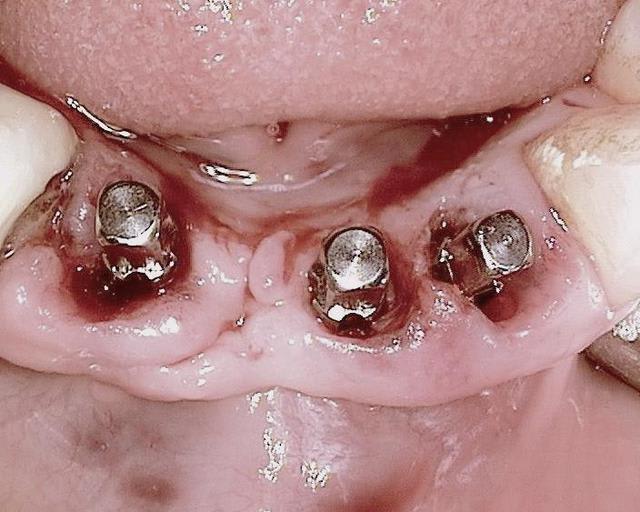

Bonjour, merci pour ta question:

46 : 10mm de longueur et 4,5mm de diamètre (parce que je n ai pas atteint la stabilité primaire avec le condenseur 3,0 la mesure 30Ncm)

45 et 36: 10mm de longueur et 3,5mm de diamètre

44, 42, 31 et 34 : 22 mm de longueur et 3,5 mm de diamètre

32 : 20 mm de longueur et 3,5 mm de diamètre

ton commentaire m a fait remarqué que je n´ ai pas mis la photo de la prothèse du cas! merci ! :-)

ci dessous

cordialement